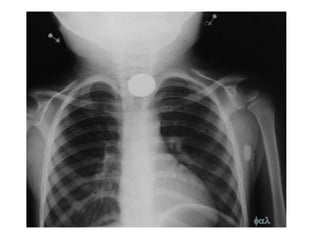

BRONCOGRAMA AEREO

BRONCOGRAMA AÉREO: